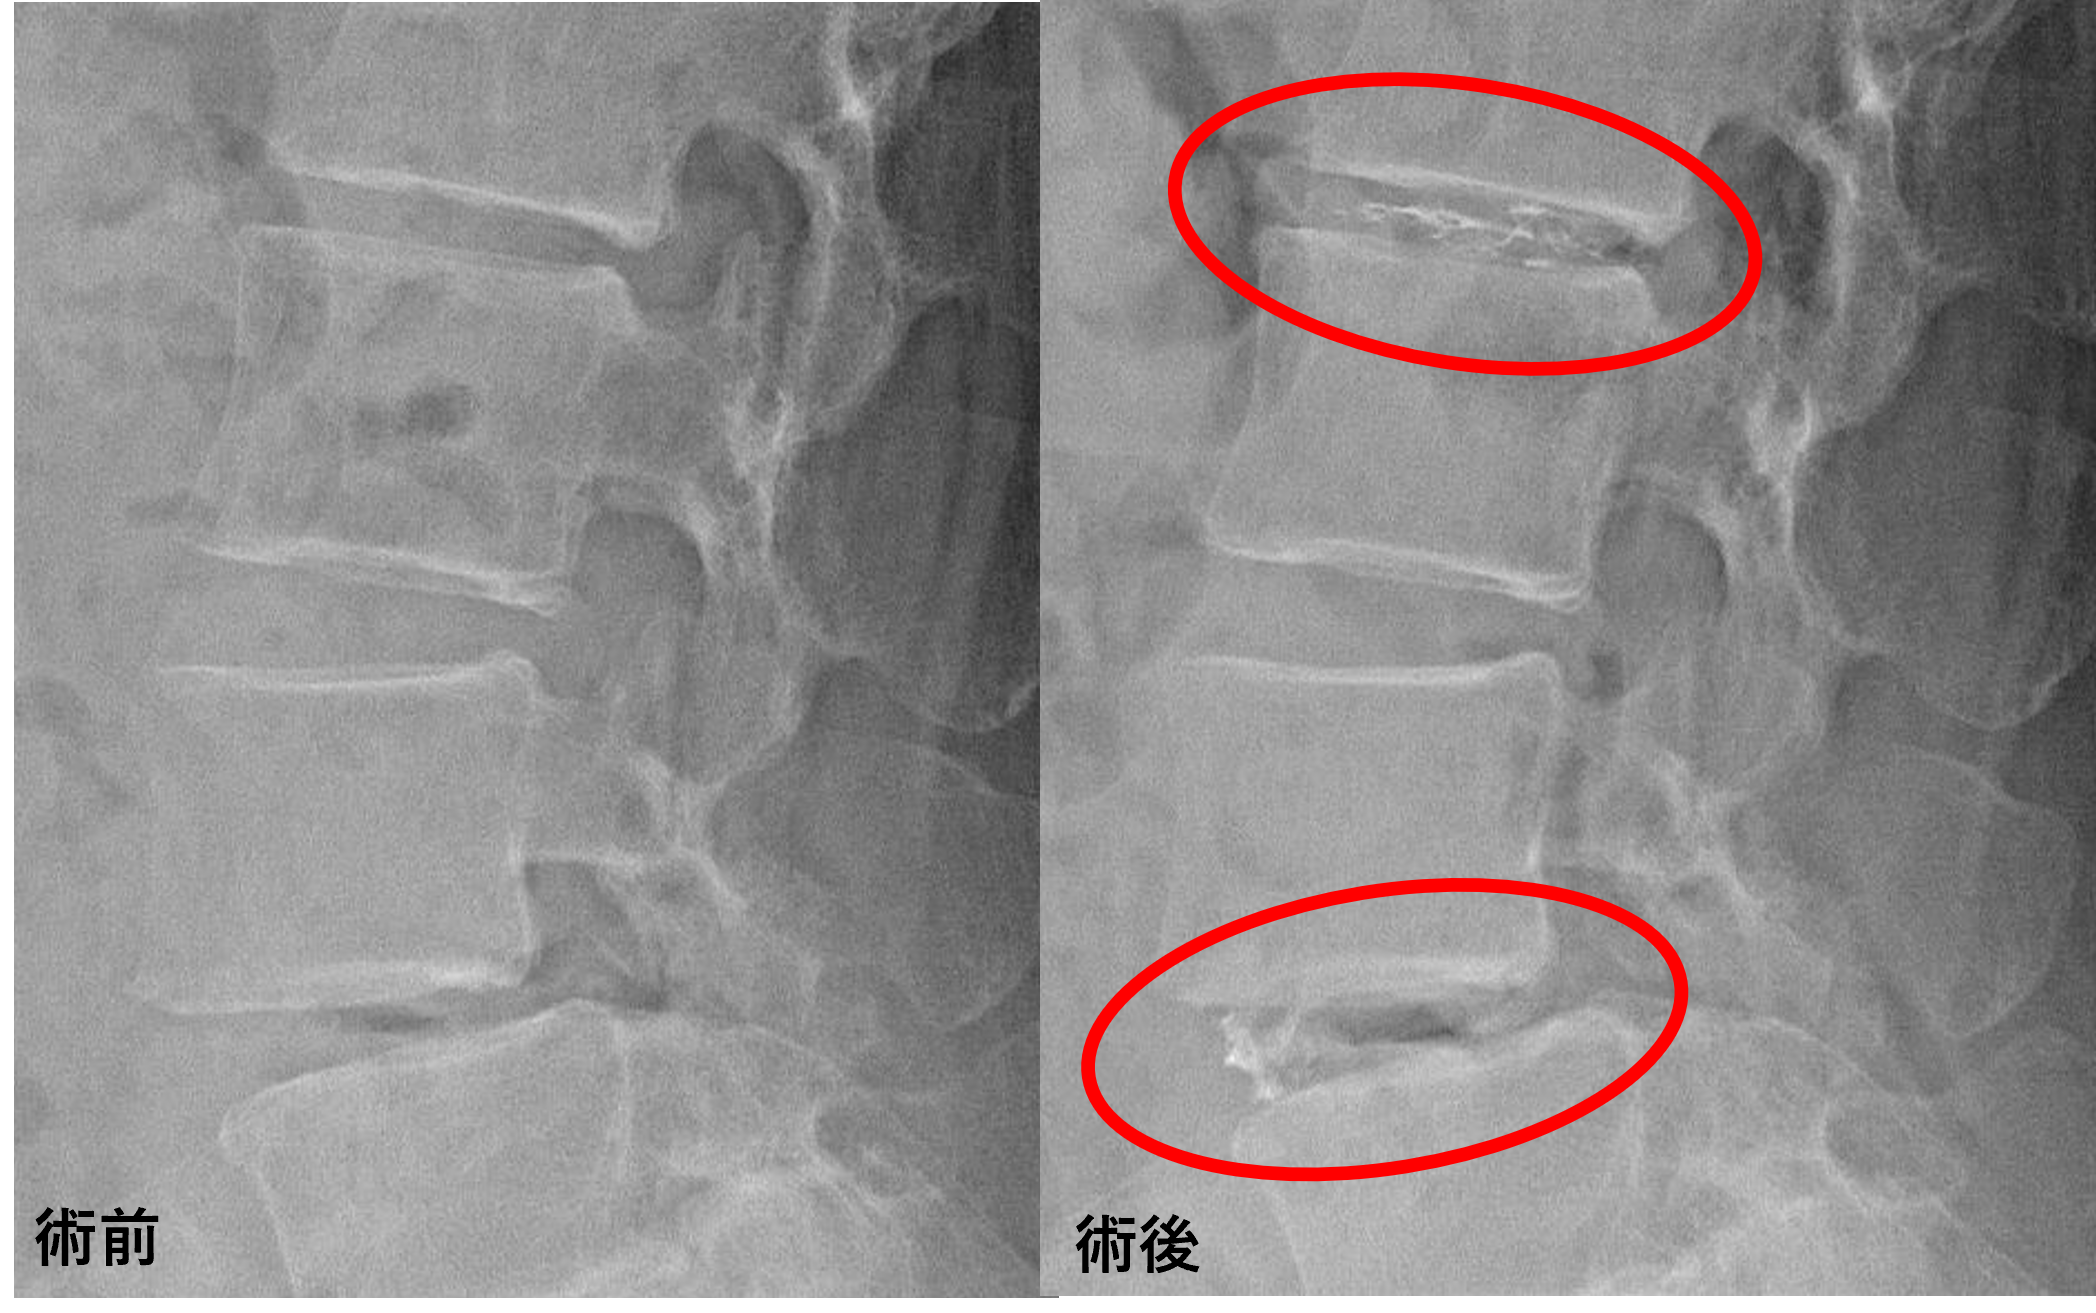

画像及び所見について

- L2/3 – 椎間板変性、膨隆、椎間孔狭窄

- L3/4、5/s – 椎間板変性、膨隆

- L4/5 – 椎間板変性、膨隆、椎間孔狭窄、脊柱管狭窄、変性すべり

以上のことが画像上認められました。

L2/3、4/5の椎間板所見による脊柱管の圧排が、症状の原因の可能性がもっとも高い。

患者様と相談の元、L2/3、4/5にセルゲル法を施行